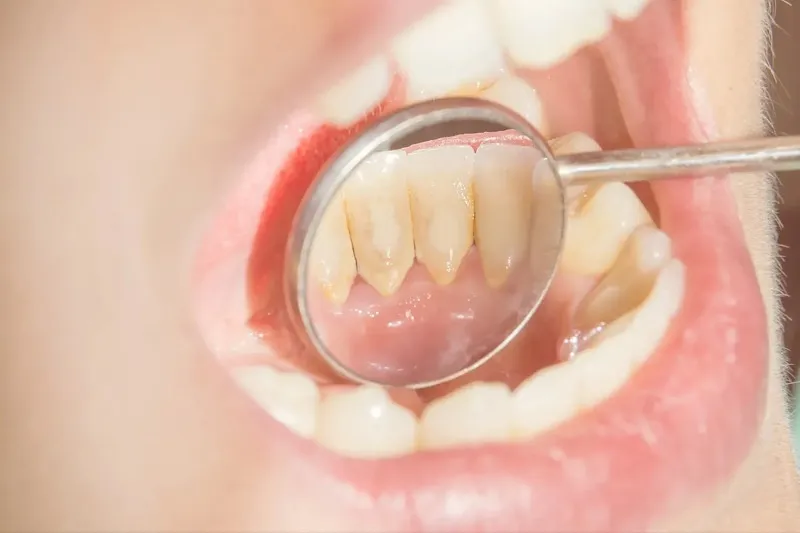

Cao răng bị vỡ là hiện tượng khá phổ biến, nhưng không phải ai cũng biết cách xử lý đúng cách khi gặp phải tình trạng này.